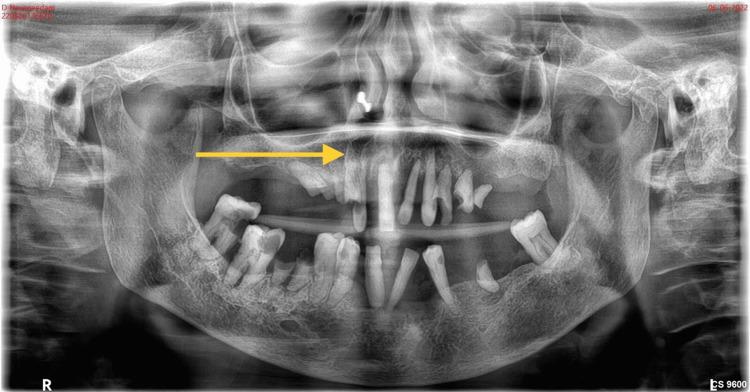

Benign fibro-osseous lesions are a group of pathological conditions characterized by the replacement of normal bone with cellular fibrous connective tissue that undergoes mineralization. The most common types of benign fibro-osseous lesions include fibrous dysplasia, ossifying fibroma, and osseous dysplasia. However, diagnosing these lesions can be challenging due to their overlapping clinical, radiological, and histological features, which can cause a diagnostic dilemma for surgeons, radiologists, and pathologists. One rare type of benign fibro-osseous lesion is the cemento-ossifying fibroma (COF), which is a definitive form of a benign fibro-osseous tumor that affects the craniofacial region, particularly the jaws (70%). Here, we present a case of COF in a 61-year-old female patient in the maxillary anterior region. Due to a clear distinction between the lesion and healthy bone, the lesion was treated with conservative surgical excision followed by curettage and primary closure. However, differential diagnosis of COF can be highly challenging for clinicians due to its overlapping features with other fibro-osseous lesions like Paget's disease and fibrous dysplasia. Ossifying fibroma and fibrous dysplasia often present a histopathological, clinical, and radiological overlap. The post-operative follow-up after eight months was unpredictable, with a radiological picture showing the increased thickness of the frontal bone, parietal bone, and maxilla with obliteration of marrow spaces, alteration of the trabecular pattern with a cotton wool/ground glass appearance, and reduced maxillary sinus space. Proper evaluation and diagnosis of fibro-osseous lesions are necessary before arriving at a final conclusion. Cemento-ossifying fibroma in the maxillofacial skeleton is uncommon, and after eight months, the recurrence rate is rare. This case highlights the importance of considering COF as a differential diagnosis for fibro-osseous lesions in the maxillofacial region and the necessity for proper evaluation and diagnosis to determine the appropriate treatment plan and prognosis. In summary, the diagnosis of benign fibro-osseous lesions can be challenging due to their overlapping features, but early diagnosis and proper evaluation are essential for successful treatment outcomes. COF is a rare type of benign fibro-osseous lesion where other fibro-osseous lesions in the maxillofacial region should be considered as a differential diagnosis, and the necessary steps should be taken to confirm the diagnosis before arriving at a final conclusion.

良性纤维-骨病变是一组病理状况,其特征是正常骨被经历矿化的细胞性纤维结缔组织所替代。最常见的良性纤维-骨病变类型包括骨纤维异常增殖症、骨化性纤维瘤和骨发育异常。然而,由于这些病变在临床、放射学和组织学特征上存在重叠,诊断起来可能具有挑战性,这会给外科医生、放射科医生和病理科医生带来诊断难题。一种罕见的良性纤维-骨病变是牙骨质-骨化性纤维瘤(COF),它是一种影响颅面部区域,尤其是颌骨(70%)的良性纤维-骨肿瘤的明确形式。在此,我们报告一例61岁女性患者上颌前部区域的COF病例。由于病变与健康骨之间界限清晰,该病变采用保守性手术切除,随后刮除并一期缝合进行治疗。然而,COF的鉴别诊断对临床医生来说极具挑战性,因为它与其他纤维-骨病变如佩吉特病和骨纤维异常增殖症有重叠特征。骨化性纤维瘤和骨纤维异常增殖症常常在组织病理学、临床和放射学上存在重叠。八个月后的术后随访情况难以预测,放射影像显示额骨、顶骨和上颌骨厚度增加,骨髓腔消失,小梁模式改变呈棉絮状/磨砂玻璃样外观,上颌窦空间减小。在得出最终结论之前,对纤维-骨病变进行恰当的评估和诊断是必要的。上颌面部骨骼中的牙骨质-骨化性纤维瘤并不常见,八个月后复发率很低。该病例凸显了将COF作为上颌面部区域纤维-骨病变鉴别诊断的重要性,以及进行恰当评估和诊断以确定合适治疗方案和预后的必要性。总之,由于良性纤维-骨病变特征重叠,其诊断可能具有挑战性,但早期诊断和恰当评估对于成功的治疗结果至关重要。COF是一种罕见的良性纤维-骨病变,上颌面部区域的其他纤维-骨病变应被视为鉴别诊断对象,在得出最终结论之前应采取必要步骤以确诊。